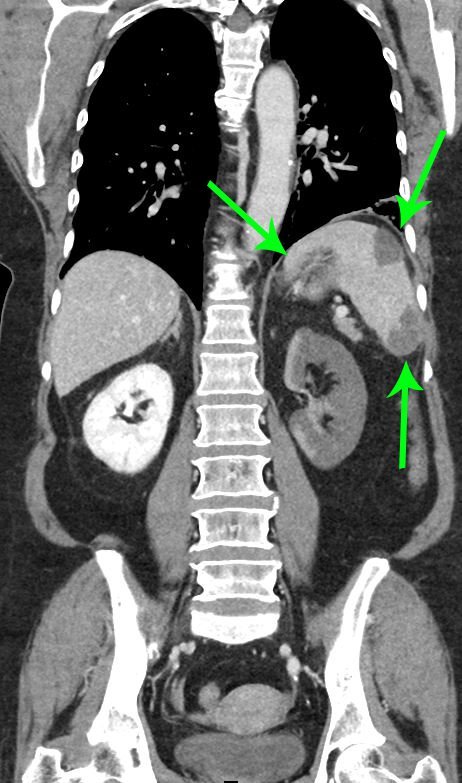

On the coronal sections of computed tomography (CT), bilateral renal infarctions (blue arrows) and several splenic infarctions (green arrows) are noted. Of particular interest, part of the clot totally occluding the left renal artery visibly extends into the aorta (red arrow). The vascular reconstruction image is remarkable for the absent left kidney, the unusual contour of the right kidney and the abnormal splenic blush.

Classic emergency medicine teaching dictates that when a patient with atrial fibrillation has abdominal pain “out of proportion” to the examination, one must consider mesenteric ischemia. Although the bowels clearly carry the highest embolic risk for abdominal viscera, other organs are at risk as well. This case illustrates a rare constellation of segmental splenic infarcts and bilateral renal infarction, with complete left renal artery occlusion stemming from multiple emboli.